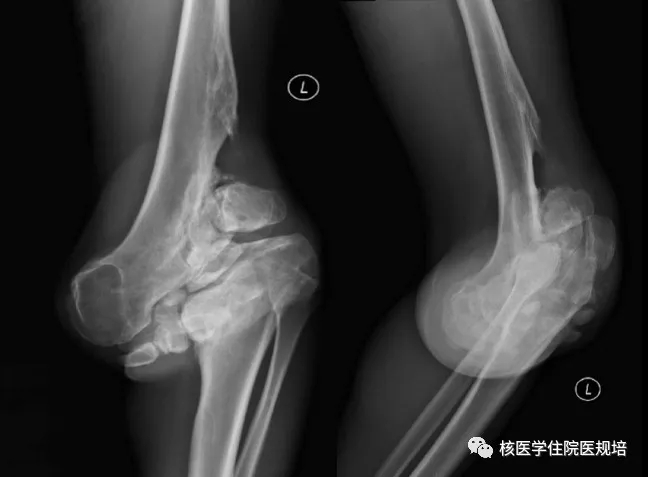

患者男性,30岁, 3个月前无明显诱因突发大小便失禁,同时伴下肢活动障碍,为进一步诊治就诊于我院。既往史:出生后诊断为先天性无痛无汗症,其他无特殊病史。查体:患者轮椅进入病房,神志清楚,对答切题;全身皮肤干燥、见多处瘢痕,皮肤痛觉缺失,指甲发育不良,脊柱生理屈度存在,无明显棘突压痛。双上肢未见明显畸形,肌力、肌张力未见明显异常。左下肢可见膝关节不规则隆起,表面不光滑,质硬,无波动感,关节屈伸正常,局部皮温正常,无皮肤红肿、破溃或静脉怒张,压痛(-);右下肢未见明显异常。双下肢感觉较弱,巴氏征(-)。实验室检查无明显异常发现。腰椎X光片及CT(图1.2)检查发现腰椎退行性变,L3、L4椎体融合,骨小梁结构模糊,L5/S1椎间盘膨出,前纵韧带钙化;多关节部位X光片示右髋关节(图3)髋臼扩大、骨质吸收,股骨头脱位,骨骺未融合,残端如刀削状,关节肿胀,内见多发碎骨片;左膝关节(图4)正常关节结构消失,关节对位差,骨端膨大,周围见多发游离骨块,股骨下段、胫骨平台见骨质破坏,关节周围软组织肿胀;右踝关节(图5)诸骨在位,胫腓骨远端膨大变形,距骨变扁,诸骨骨质密度弥漫减低,骨小梁稀疏,内外踝边缘可见骨质增生;关节间隙狭窄。为进一步了解全身骨病变情况行99mTc-MDP全身骨显像(图6)。

图4.